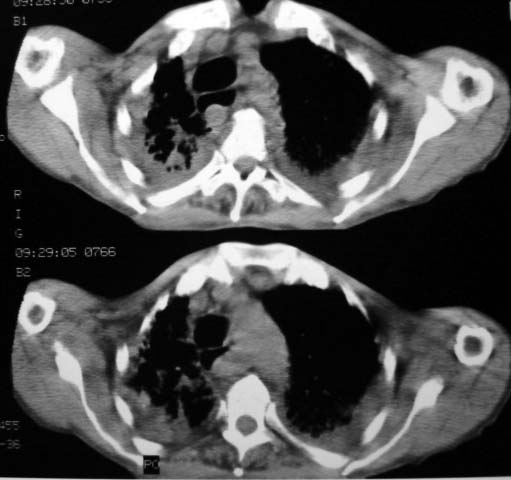

男,85岁,发热2月, 血常规:hgb99g/l.rbc2.55×1012/l.wbc3.8×109/l.n78.2%  l20.7% m1.1%.  hct26.3% .血沉20mm/hg.痰检结核杆菌阴性。ddp阳性。痰少粘稠色白。无咳血。

1.右上肺陈旧性肺结核灶;

右上肺陈旧性肺结核灶,双肺感染灶〔大部份纤维化〕,肺气肿.

双肺继发型肺结核,肺纤维化,肺气肿,胸膜肥厚黏连。